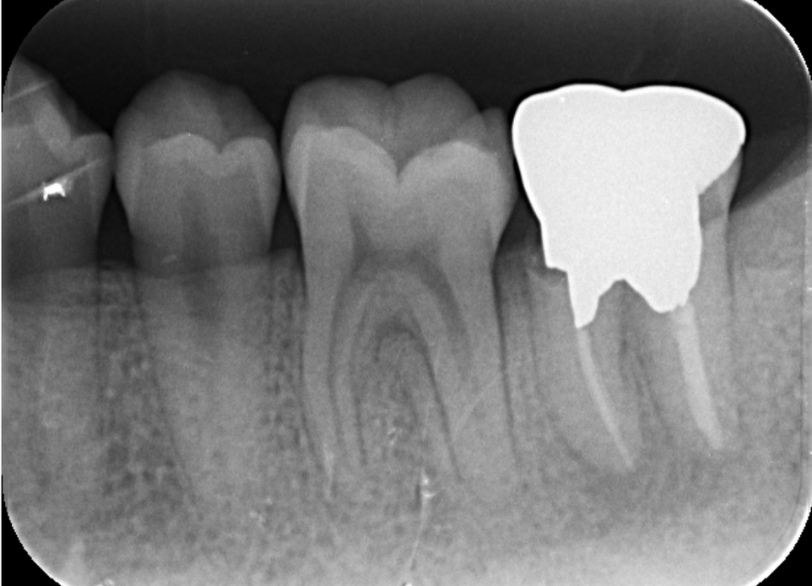

移植歯に対するエムドゲイン塗布および形状確認(抜歯時に破折してないかなど)

右上8を左下7へ移植完了

この後、根管治療、治療に必要な神経開口部の被覆を行いました(経過2年の状態は良好)